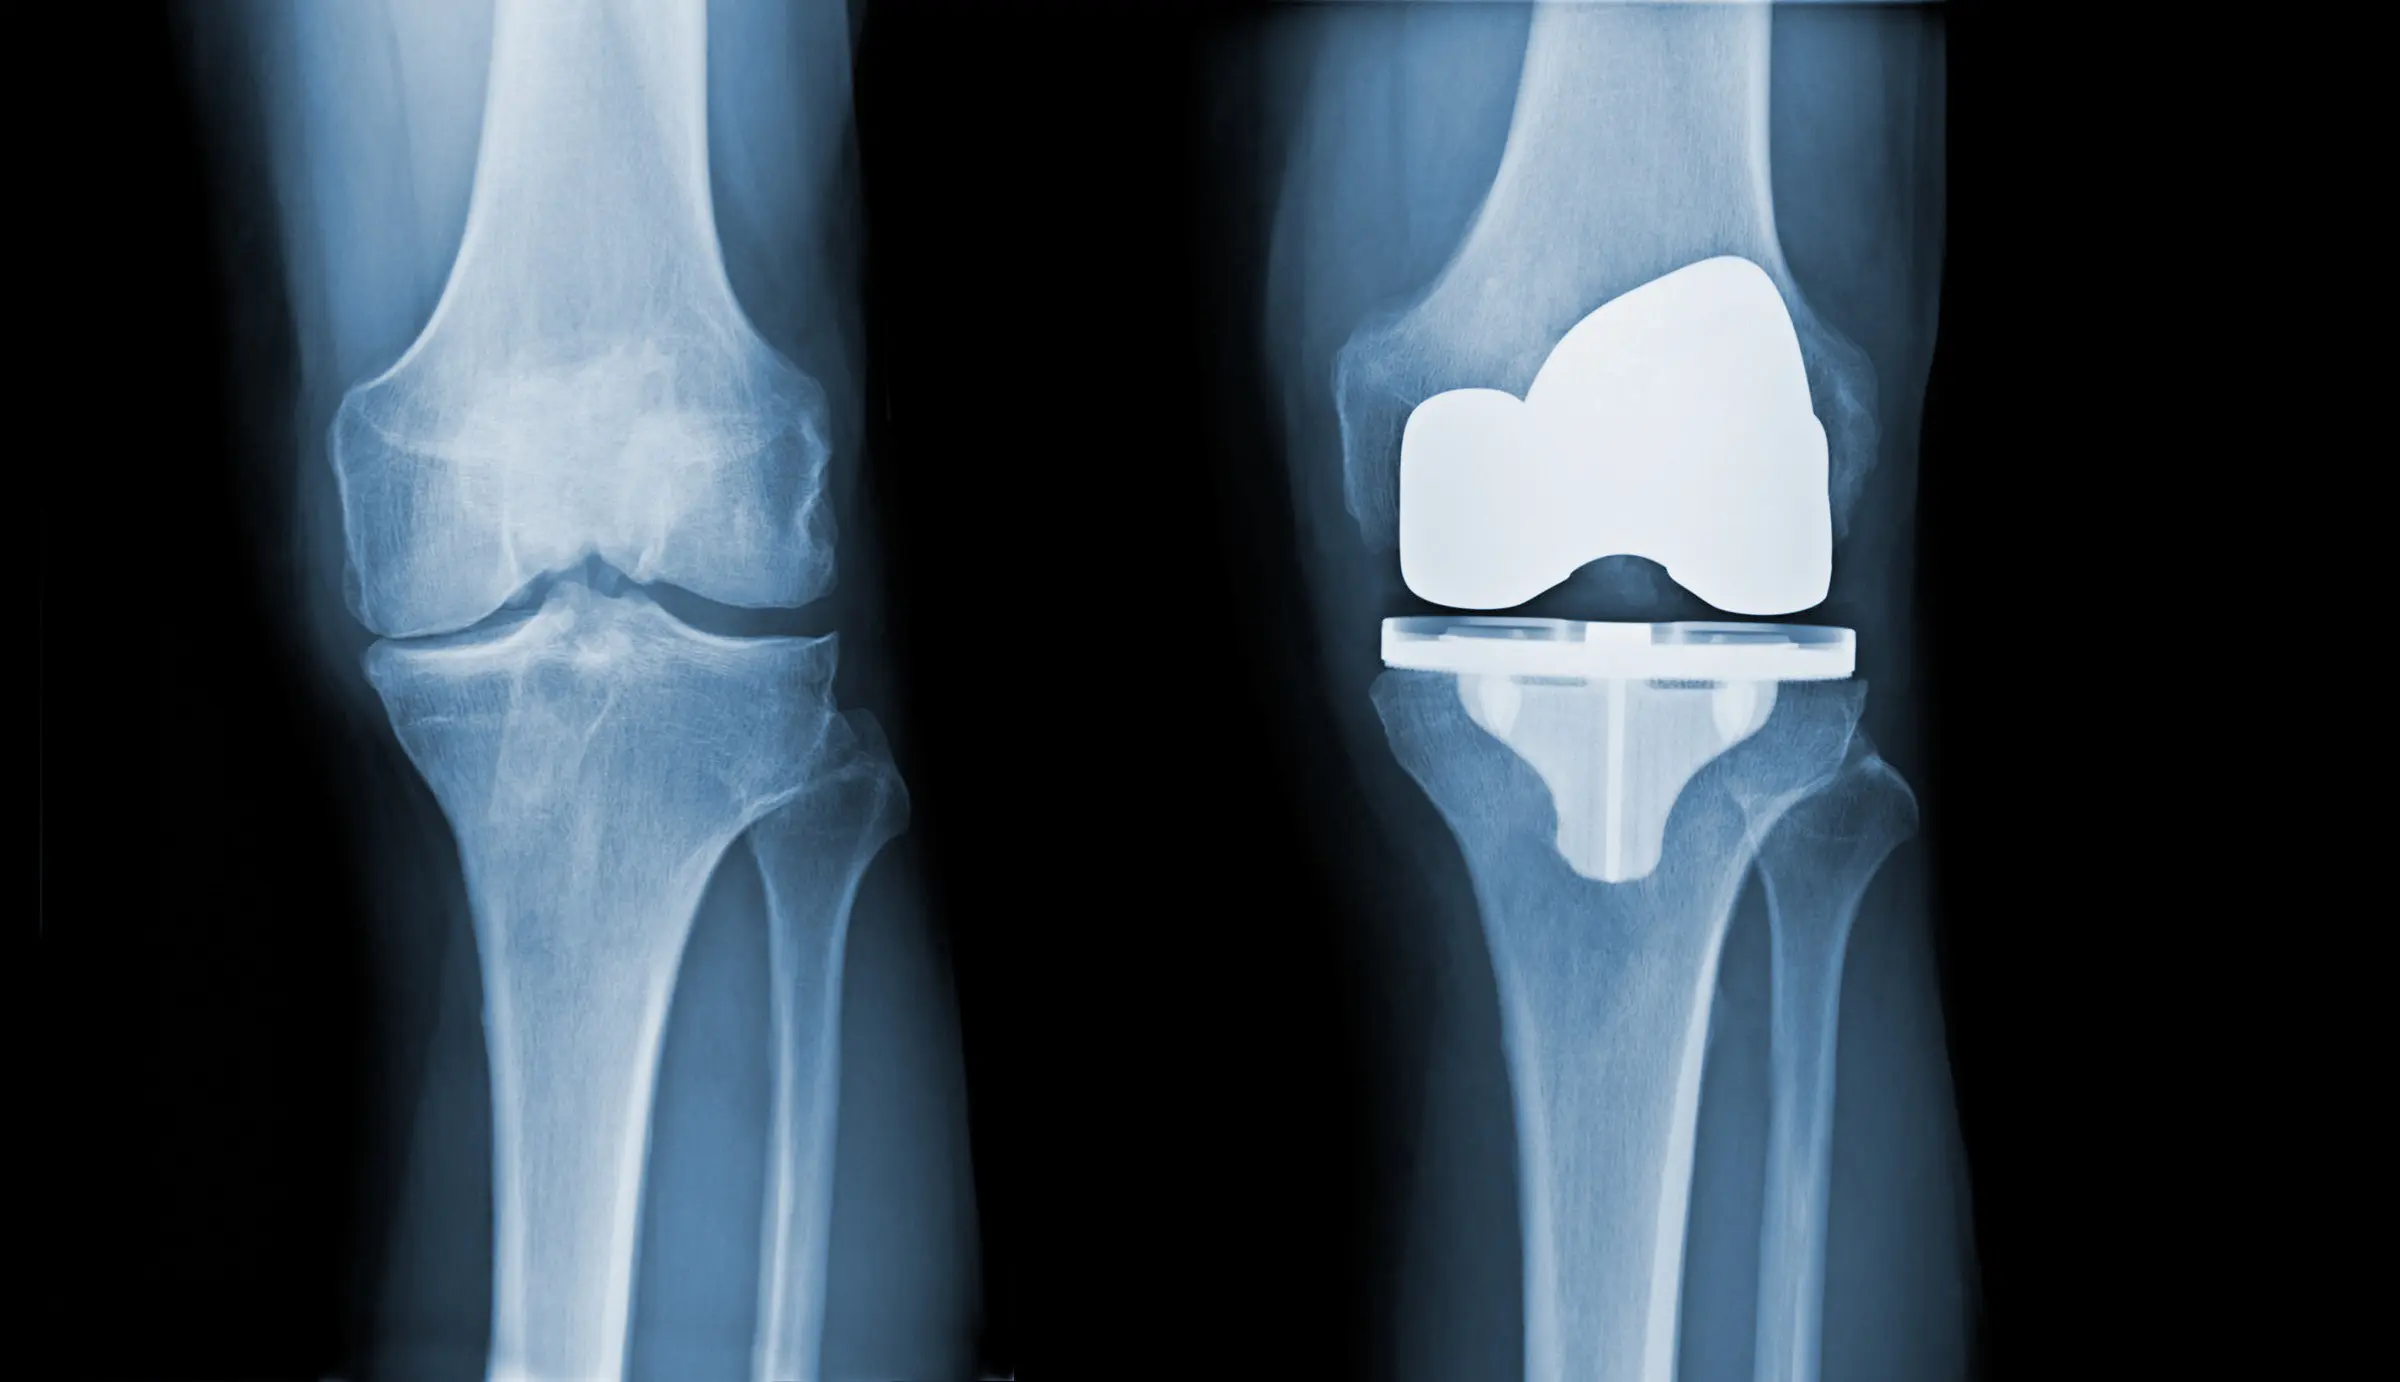

Zdjęcie RTG kolana

Leczenie choroby zwyrodnieniowej